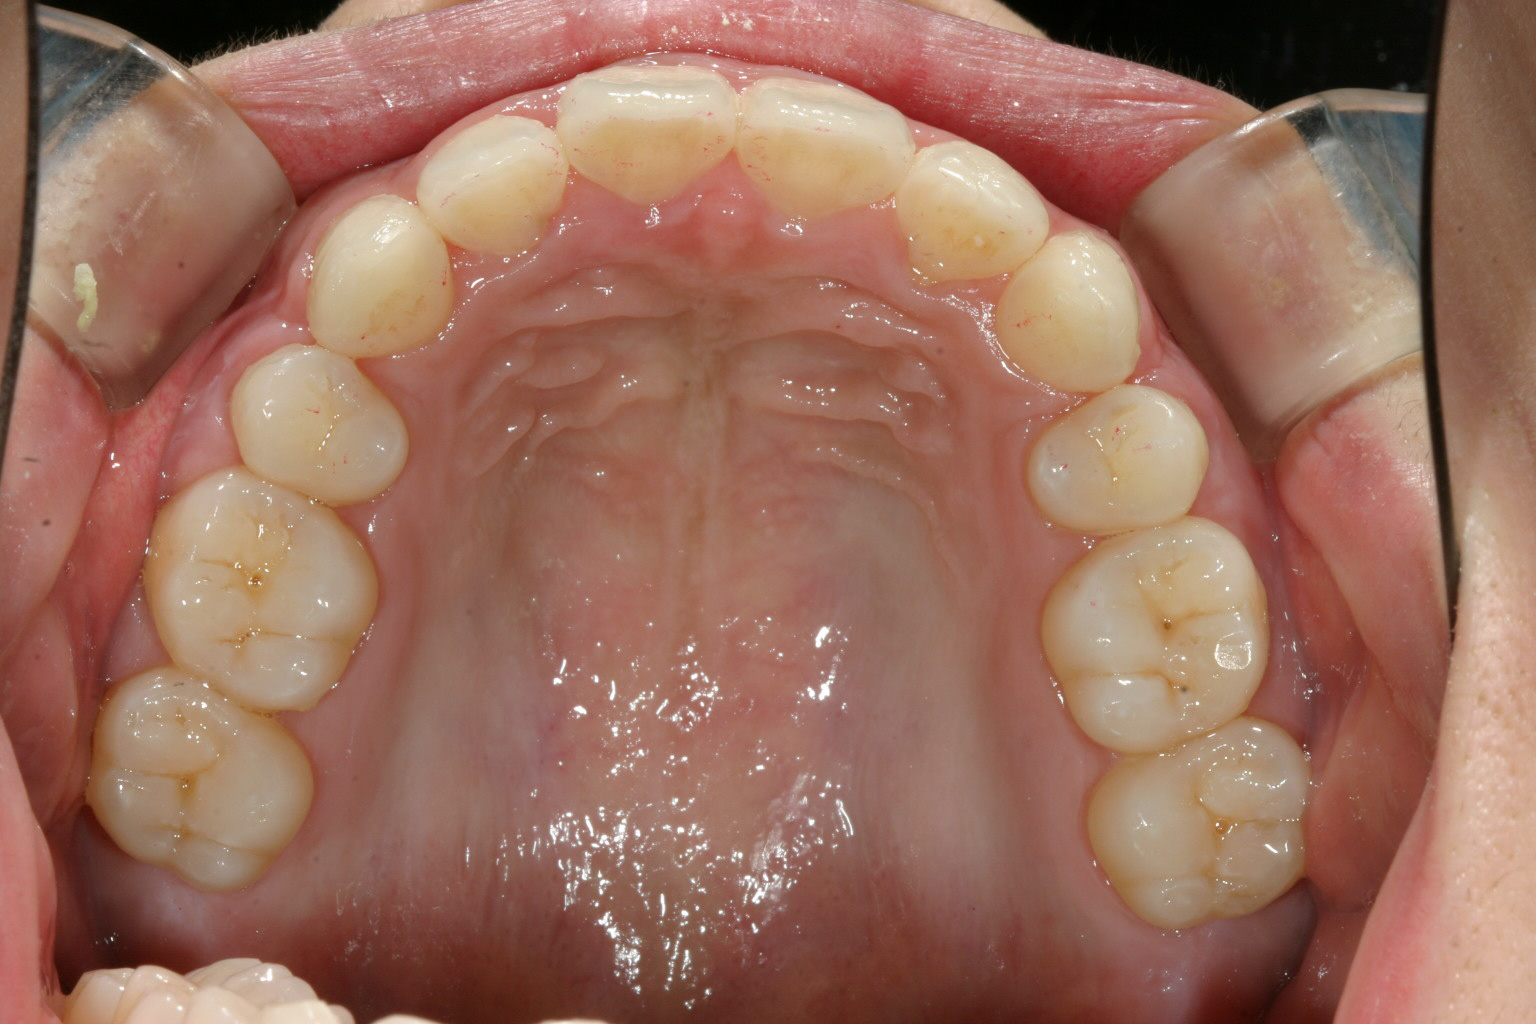

上の写真と比較してください。 かなり引っ込みました。

V字型のアーチをU字に改善するのと小臼歯抜歯する事でインビザラインで最大限に引き込めました。

かなり綺麗に仕上がったと思います。